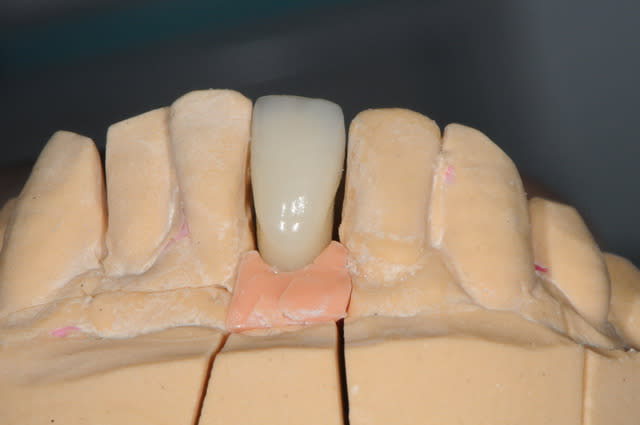

je me permet de ressusciter ce poste car j'ai placé la prothèse il y a un mois.

photo 1: début du cas

photo 2: fin d'intervention

photo 3: j+3mois

photo 4 +5: prise d'empreintes

photo 6-7-8-9: couronne finie.

merci de votre attention :)

PS: le patient ne veux pas faire celle d'à coté.

grr, moi ça me démange...